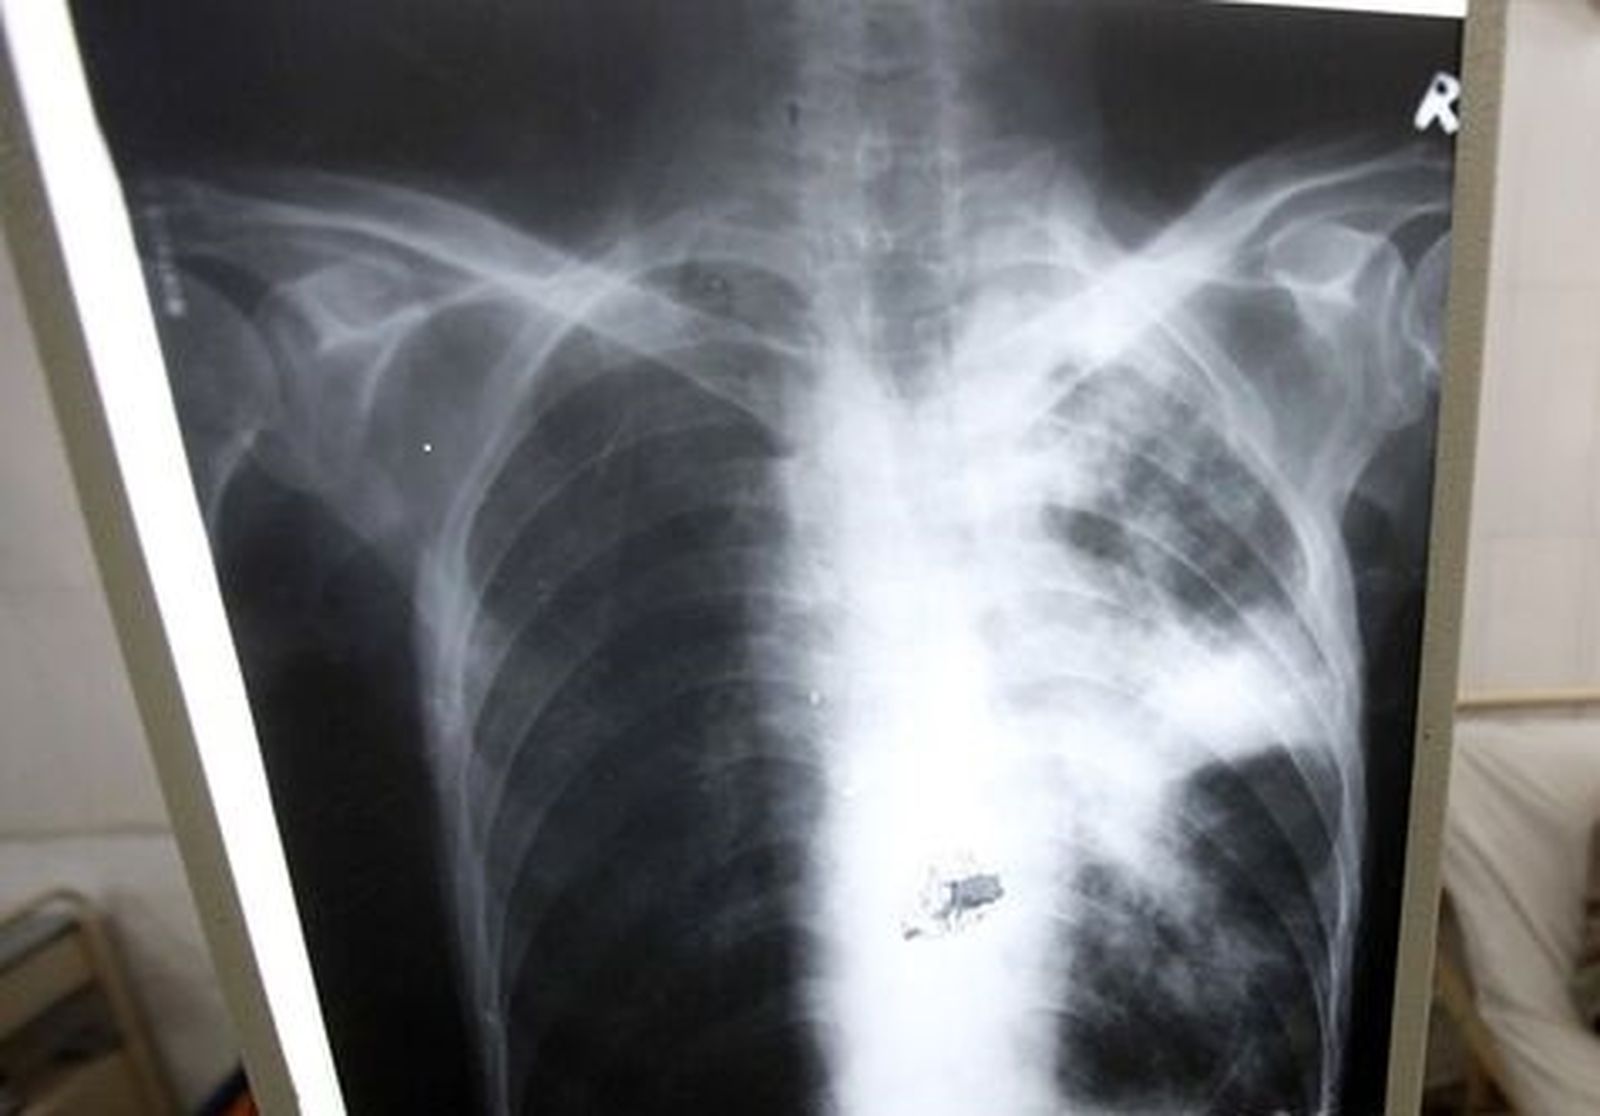

Tuberculosis.

Tuberculosis. / R. D.